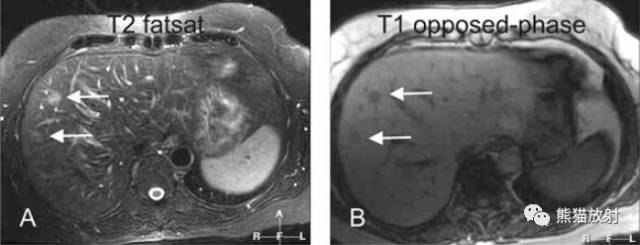

各序列信号特征

T2 fatsat:T2WI压脂,转移灶呈高信号;

T1 in-phase:T1同相位,病灶呈低信号;

ART:动脉期,病灶明显不均质强化;

DEL:延迟期,持续不均质强化。

A~D:影像表现如上所述。

E:T2WI,病灶呈稍高信号;

F:反相位,脂肪肝,病灶周边线样高信号提示受压的肝实质;

G:冠状T2WI,病灶呈较高信号;

H:冠状延迟期,转移瘤持续不均质强化。